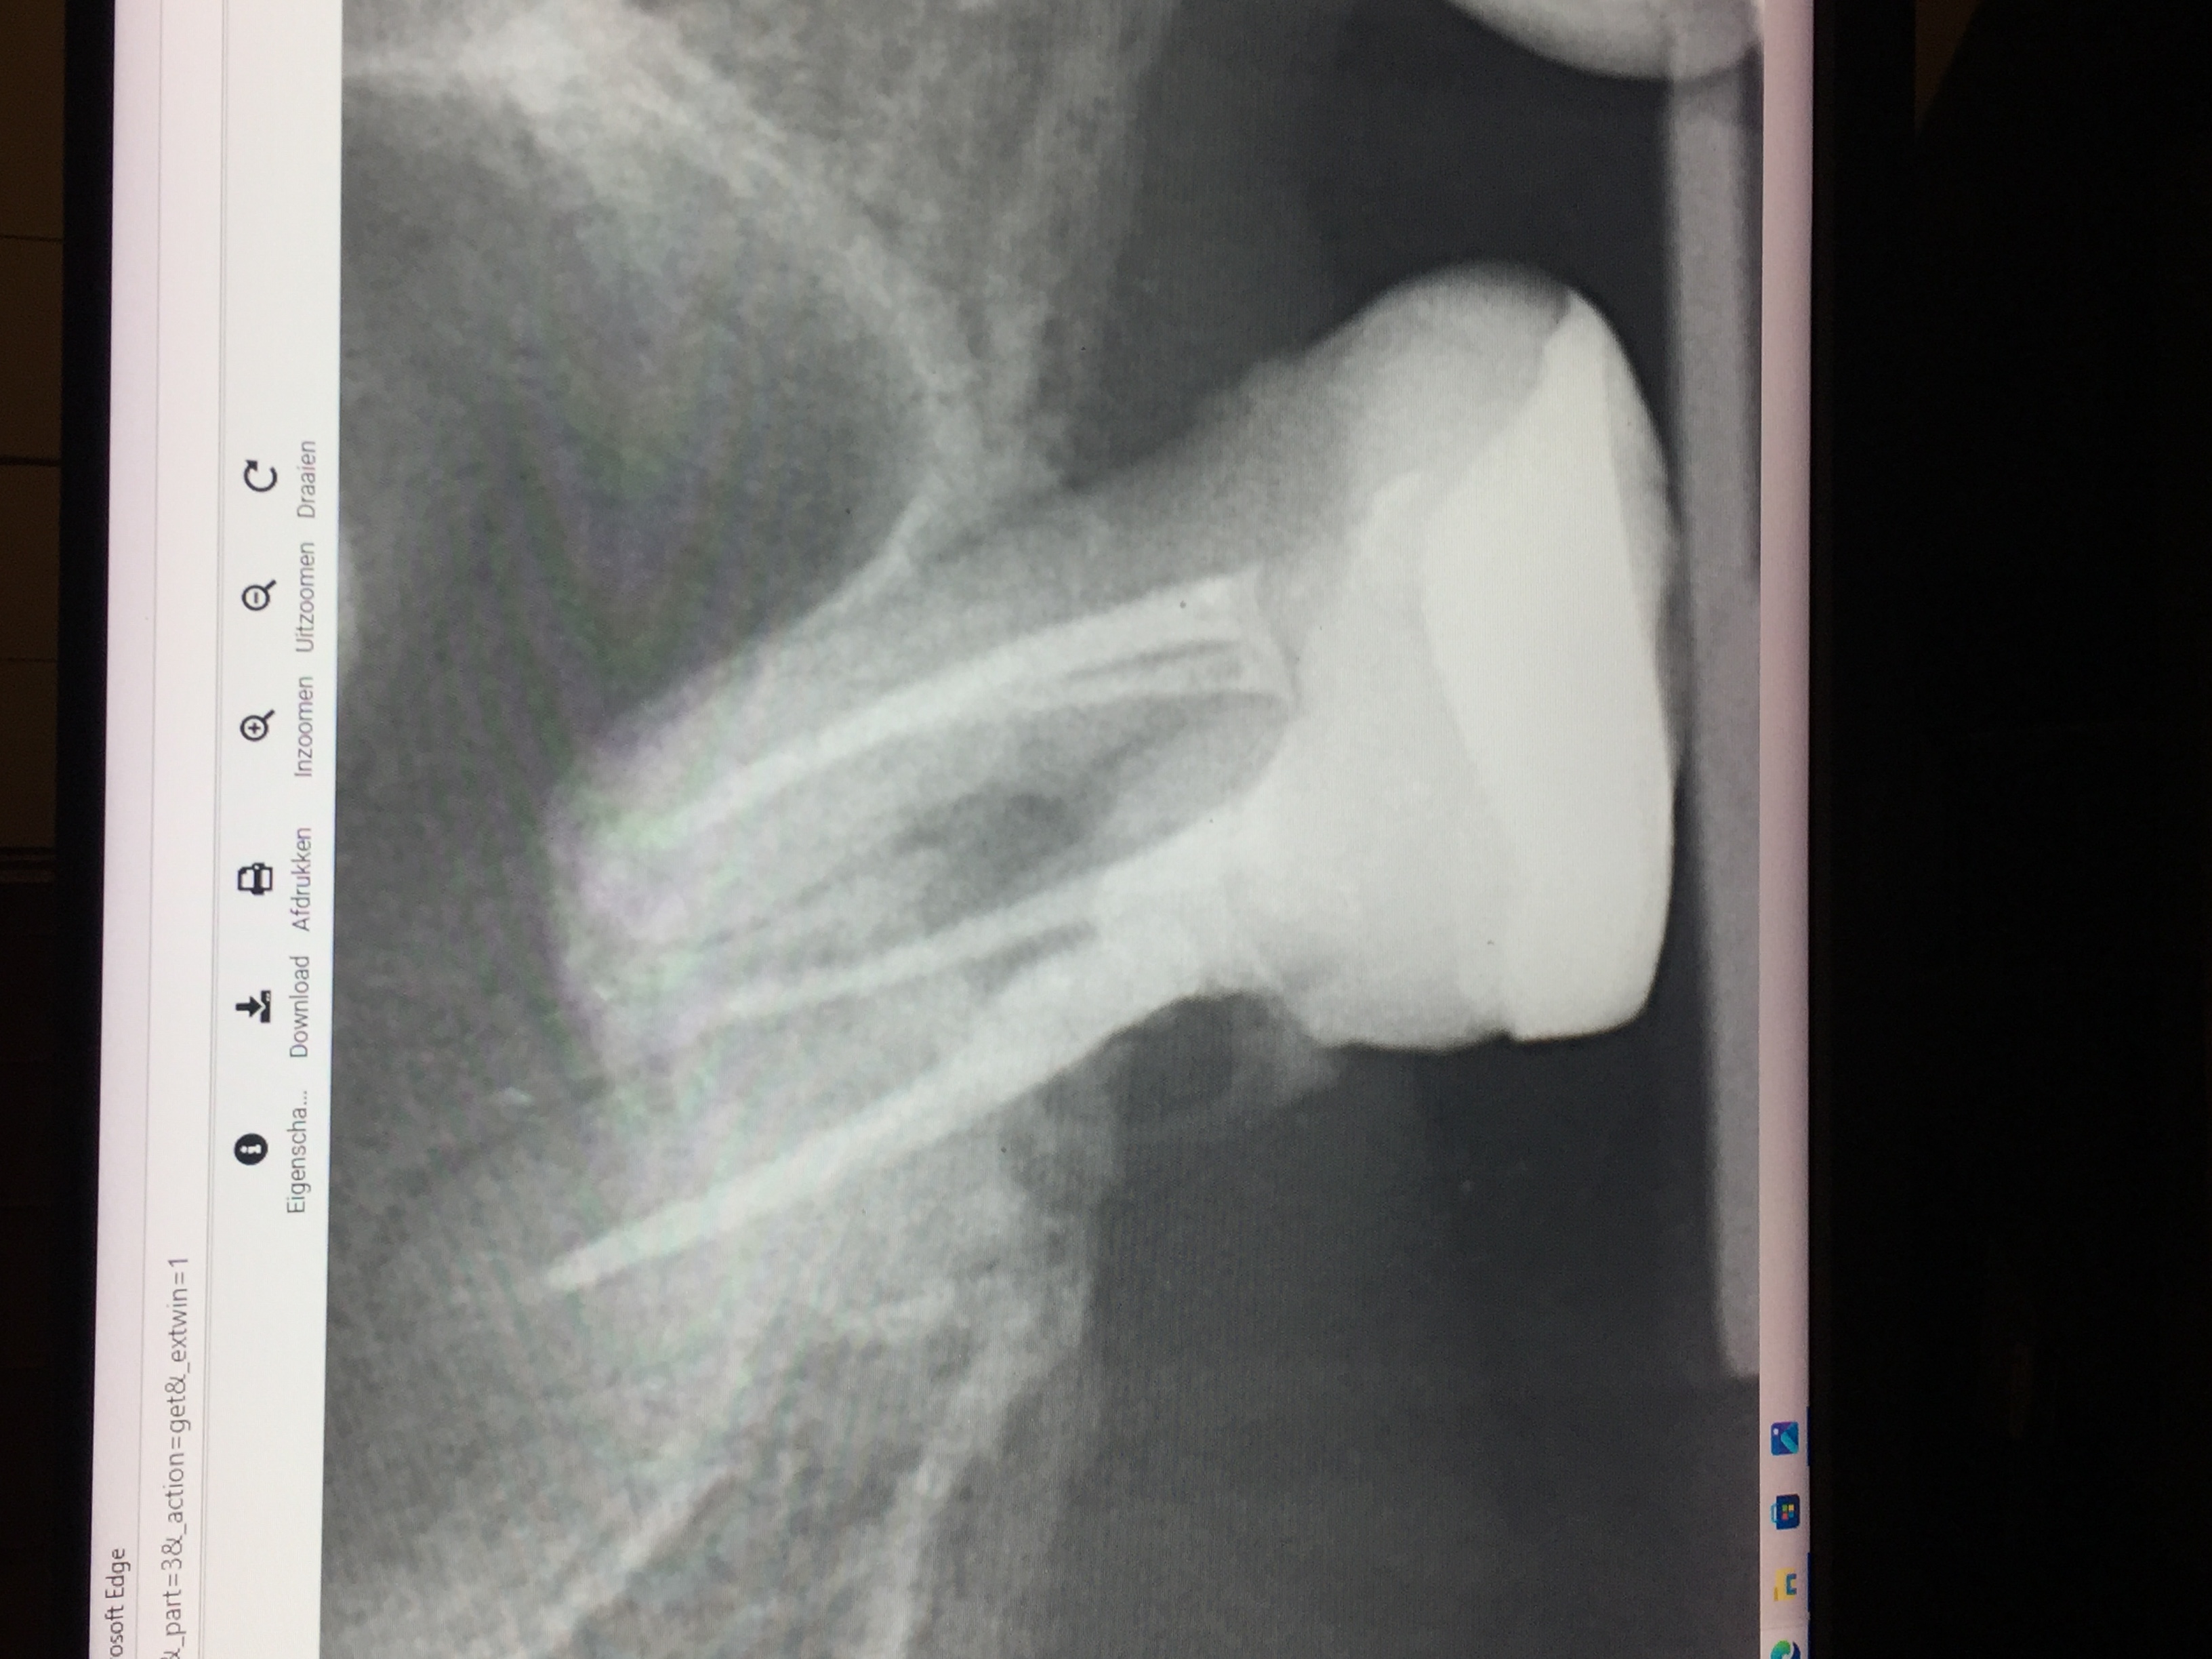

Beste Tandartsen. ik heb een kies die 10 jaar gelden een wkb heeft gehad bij een endodontoloog nog.

de kies was altijd nog wat gevoelig zwakke kies maar met kauwen geen problemen.

meestal kreeg ik last in het voorjaar van kiespijn .en de tandarts maar foto's maken en zag jaren niks. nu een week geleden ineens erge last van mijn kaak aan de kant waar de kies zich bevind. trok met steken in het voorhoofd ook had ik bloed in het neusgat aan de kant van de kies. het andere neusgat dus niet. .voelde mij echt niet lekker. leken wel aanvallen want daarna ging het telkens weer wat beter en zakte het weer. bij warm eten klaarde het vreemd genoeg helemaal op dat gaf verlichting. ik zit nu een week aan de Naproxen en het is nu weer stabiel. maar ik had weken ervoor al veel last van mijn buik gehad. ineens ook pijnsteken in de buikstreek en maag. wist niet waardoor dacht misschien een virus ofzo en dat het dan nu overgesprongen was naar mijn kaak.. ben een keer een maand geleden naar de huisarts voor de buikklachten geweest . die dacht omdat ik melk dronk het daar aan lag maar bleek dus achteraf niet zo te zijn geen last meer van en drink gewoon elke dag mijn melk.

afijn vanmiddag naar de tandarts geweest en op de foto zag de tandarts ineens dan mijn wortel was opgelost. ze voelde ook met een haakje en had daar aan de achterkant wel wat diepe pockets. ze dacht aan een breuk in de wortel maar ik heb geen last met kauwen erop. alleen als ik met mijn tong op het kaakbot achter de kies druk dan voel ik wat. .

Ik had het met mijn tandarts al over het plaatsen van een implantaat gehad. dit wilde ik eigenlijk 10 jaar geleden al toen ik last van deze kies had maar toch naar een endodontoloog ben gegaan voor herbehandeling nadat mijn tandarts de wortel perforeerde bij her behandeling omdat hij deze maar voor de helft gevuld had met kanaalvulling. de wortel die nu dus aan het verdwijnen is. ik weet niet hoe dit verdwijnen komt na 10 jaar maar weet wel dat de boor tijdens de het perforeren destijds met een klap vastsloeg in deze wortel. kan dat er iets mee te maken hebben?? maar waarom dan pas 10 jaar later vraag ik mij af? of is dit een proces van 10 jaar? de endodontoloog heeft de perforatie toen met MTA gedicht. ze was erg positief erover.

eigenlijk had de tandarts dit gat al gelijk moeten dichten maar die had geen microscoop en wilde de kies niet meer aanraken. ik zie wel op de foto waar de wortel onderbroken is precies zit waar de kies in het verleden is geperforeerd. zie andere foto van direct na de endo 10 jaar geleden.